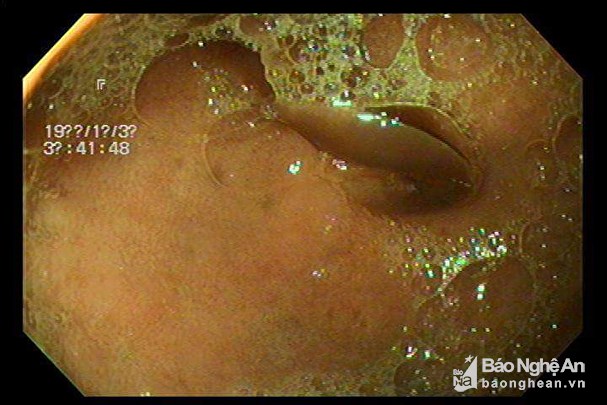

Gắp thành công sán lá gan trong dạ dày bệnh nhân 33 tuổi

Một phòng khám ở huyện Quỳ Hợp (Nghệ An) cho biết, vừa phẫu thuật gắp bỏ con sán lá gan trong dạ dày - tá tràng cho anh Lô Văn T (33 tuổi) ở xã Châu Cường.

Bệnh nhân đến phòng khám với triệu chứng đau bụng âm ỉ, người mệt mỏi, khó chịu trong người, bác sĩ đã cho bệnh nhân nội soi dạ dày - tá tràng, qua đó xác định anh T có con sán ở tá tràng và chỉ định phẫu thuật để gắp con sán lá gan ra khỏi cơ thể.

Sau khoảng 10 phút phẫu thuật, bác sỹ của phòng khám này đã gắp thành công con sán dài 1,5cm, rộng 1cm trong người anh T.

Hình ảnh siêu âm sán lá gan. Ảnh: Báo Nghệ An. |

“Sau khi gắp sán ra khỏi cơ thể, bệnh nhân phải dùng thuốc điều trị đặc hiệu để diệt những trứng sán còn tiềm ẩn trong người bệnh nhân bởi trường hợp này nếu không được điều trị thì về lâu dài trứng sán sẽ đi vào trong ruột, rồi vào gan tạo áp-xe hoặc di chuyển xuống đường mật trú ngụ”, bác sĩ Nguyễn Hồng Vui chia sẻ.